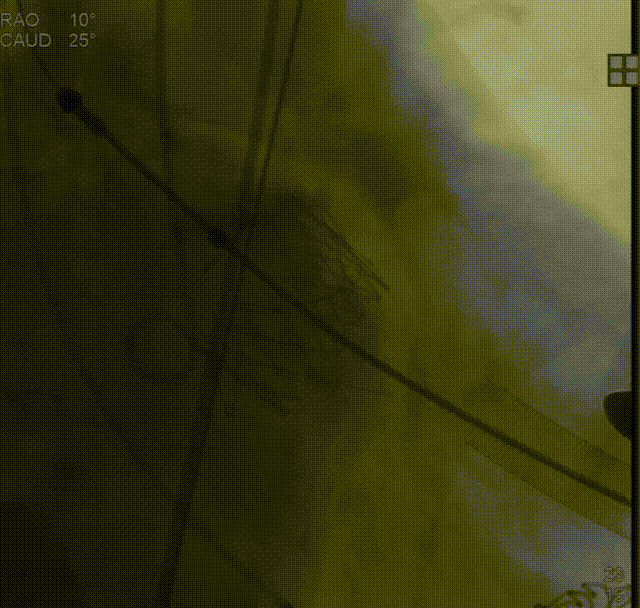

右冠造影,显示近段重度狭窄:

左冠造影未见明显狭窄:

于右冠植入冠脉支架一枚,冠脉血流通畅:

定位件入窦后造影:

降落瓣膜件:

140bpm快速起搏下释放瓣膜:

复查根部造影,未见明显反流: